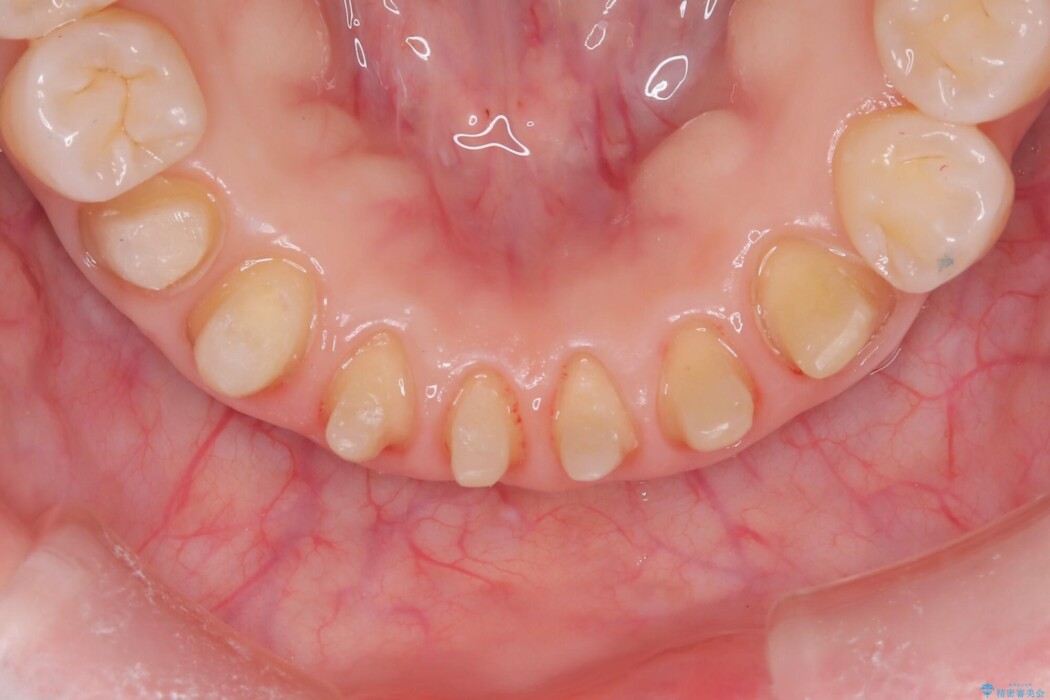

以前に治療した前歯部分に痛みがあり調べてほしいとのことで来院されました。

検査の結果、根っこに細菌が感染して病気になってしまっていました。

よって根管治療を行って洗浄・消毒(細菌の除去)をし、被せ物を装着する治療としました。

本症例ではオールセラミックスペシャルでの被せ物治療をしております。